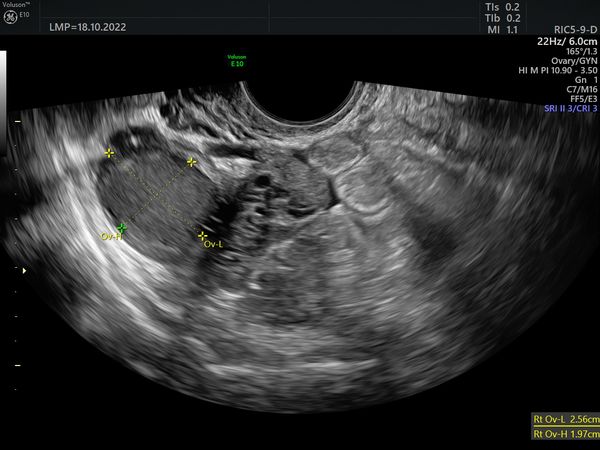

Пациентке сделали УЗИ органов малого таза на аппарате экспертного класса Voluson E 10. Согласно обследованию:

- Правый яичник. Объём 16,9 см3. Увеличен за счёт двух округлых образований с гладкими контурами. Размер первого 26 × 20 × 25 мм, объём 7 см3. Второго — 14 × 12 × 13 мм и 1,1 см3 соответственно. Содержимое образований по типу «матового стекла», акустическая тень не определяется. При цветовом доплеровском картировании (ЦДК) васкуляризация 1 балл, это значит, что образования аваскулярные (в них нет кровеносных сосудов). Количество фолликулов 8 (норма).

- Левый яичник. Объём 6,58 см3, не увеличен. Количество фолликулов 6 (норма), размер доминантного фолликула 14 мм.

Объёмных образований в малом тазу не определяется.

Эхографические признаки однокамерных образований правого яичника (эндометриомы). O-RADS II (доброкачественный процесс, риск злокачественного новообразования меньше 1 %).